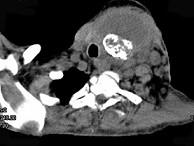

问题 女,64岁,双甲状腺占位40余天。如图所示甲状腺病灶应诊断为()

选项 A.结节性甲状腺肿 B.甲状腺腺瘤 C.甲状腺癌并淋巴结转移 D.甲状腺转移瘤 E.甲状腺结核

答案 C